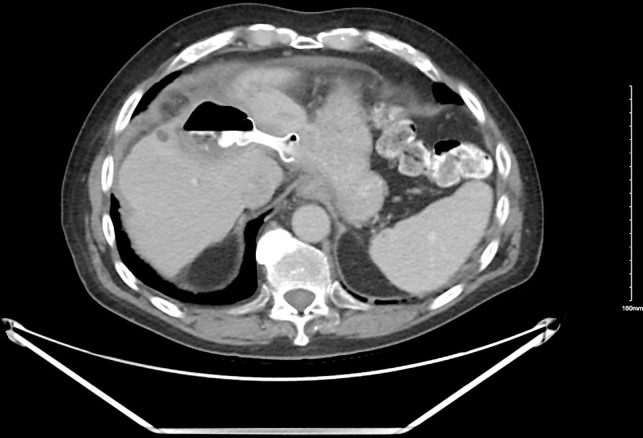

Case presentation: Three patients, average age 75 years (two men, one woman), underwent EUS-guided drainage using LAMS for an infected liver cyst, infected liver hematoma within a hepatocellular carcinoma lesion, and a symptomatic simple liver cyst, respectively. All the hepatic fluid collections were in the left hepatic lobe and had an average diameter of 11 centimeters (cm). Only the female patient with a symptomatic cyst had prior percutaneous drainage. Successful LAMS placement was achieved in all cases. Clinical success, defined as cyst resolution or significant size reduction, was observed in all patients. The superinfected liver cyst showed complete resolution, yet the stent remained in place as the patient transitioned to hospice and subsequently passed away. In the case of the superinfected liver hematoma, the stent was removed after 2 months. No recurrence was observed in follow-up imaging 8 months later, and the patient passed away. The symptomatic simple liver cyst patient had the stent removed 15 months later, with no recurrence in imaging 11 months of post-stent removal.

Conclusion: EUS-guided LAMS placement emerges as a less invasive and viable option for treating symptomatic and/or infected hepatic fluid collections compared to surgery or percutaneous drainage. While it may be a preferable choice in institutions with the requisite expertise, further studies are essential to establish its definitive role as a first-line intervention.